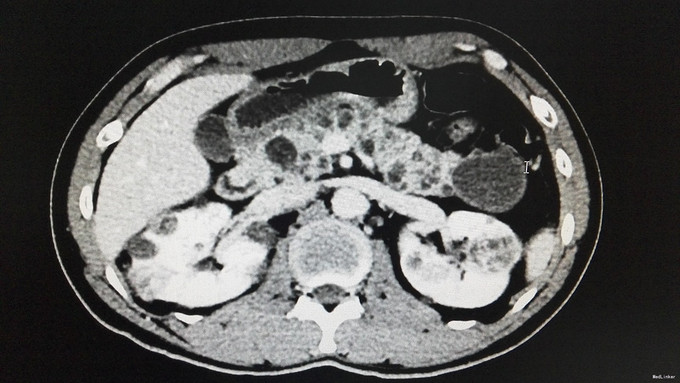

查体:背部后正中线上长7cm手术瘢痕。双肾区无红肿、隆起,左肾区压痛、叩痛,右肾区无压痛、叩痛,左肋脊点、肋腰点压痛,右肋脊点、肋腰点无压痛。左侧上中输尿管点压痛,右侧上中输尿管点无压痛,膀胱区无压痛。辅查:门诊CT示:1、胰腺多发囊肿,双肾多发肾癌,双肾多发囊肿,考虑VHL综合征。2.肝S2/4异常强化灶,考虑异常灌注。家族史:父亲肾癌去世。

诊断:VHL综合征

VHL综合征就是“Von Hippel-Lindau综合征”的简称,即CNS血管母细胞瘤合并肾脏或胰腺囊肿、嗜铬细胞瘤、肾癌以及外皮囊腺瘤等疾病。 VHL综合征是一种罕见的常染色体显性遗传性疾病,疾病是因位于染色体3P25.3的VHL抑癌基因发生突变所致。VHL的临床表现和症状包括血管瘤、血管母细胞瘤、嗜铬细胞瘤、肾细胞癌,胰腺囊肿(胰腺浆液性囊腺瘤)以及咖啡牛奶斑。VHL综合征患者平均寿命不超过49岁。其主要死亡原因是中枢神经系统血管母细胞瘤破裂出血、肾细胞癌和嗜铬细胞引起的恶性高血压。本例患者脊髓血管母细胞瘤,肾脏或胰腺囊肿,肾癌,结合家族史诊断VHL基本明确。 治疗上,中枢神经病变根据部位行手术或X刀、伽玛刀治疗。嗜铬细胞瘤应手术切除。肾细胞癌的治疗与散发性肾细胞癌有所不同,由于前者常为双侧多发,肿瘤生长较慢,转移较晚,故即使为单侧肾癌,也应尽量行保留肾单位的肿瘤切除手术,因为对侧也有在今后发生肾肿瘤的可能。多年临床观察发现,双侧全肾切除会诱发或加快其它部位的VHL肿瘤的生长,主要认为是由于移植术后的免疫抑制治疗和应用透析的结果。VHL综合征胰腺囊肿无恶变倾向,应不予处理。 VHL基因突变的人群携带率估计为3/10万左右,外显率接近100%。其遗传特征为常染色体显性方式,子女有50%机率发病,故对其子女也应严密随访。